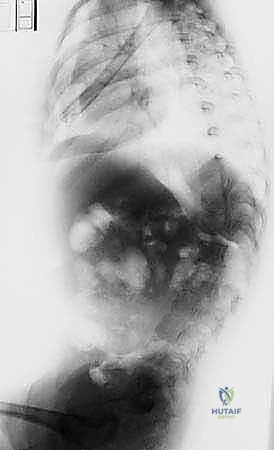

- الأشعة السينية (X-rays) البانورامية: يتم أخذ صور للعمود الفقري بالكامل من الأمام والخلف والجانب (أثناء وقوف الطفل أو جلوسه إذا كان لا يستطيع الوقوف). يتم من خلالها قياس "زاوية كوب" (Cobb Angle) لتحديد شدة الانحناء.

- التصوير المقطعي المحوسب (CT Scan) ثلاثي الأبعاد: يوفر رؤية دقيقة للتشريح العظمي المعقد، وهو ضروري جداً للتخطيط الجراحي قبل زراعة قضبان النمو لتحديد أماكن وضع المسامير بدقة متناهية.